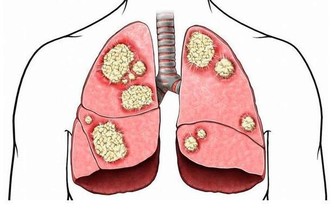

82%的上班族 便秘、消化不良

千禧之愛健康基金會,與國立成功大學醫學院附設醫院小兒部暨小兒腸胃科楊燿榮主任,進行調查發現,全台有高達82%的上班族受「偽國際作息」影響,飽受便秘、消化不良、腹脹、腹瀉及胃食道逆流等腸胃問題所苦,出現腸胃問題比例明顯高於生活作息正常的受訪者,因此提醒,長期作息時間混亂,對健康影響甚鉅,不可小覷。